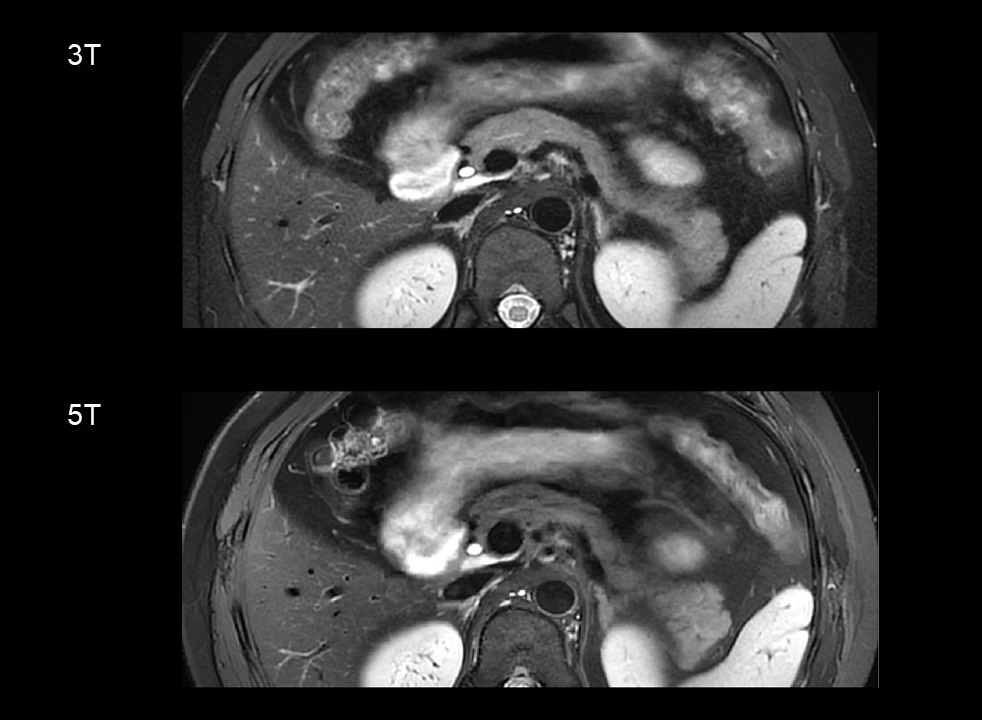

Figure 1-3 shows an example of 5T MRI and 3T MRI for each sequence. Interobserver agreement in image quality and artifacts was substantial to excellent for all sequences (κ > 0.7). Compared to the 3T examination, T1-weighted and DWI sequence at 5T showed significantly better image quality and comparable artifacts. For T2-weighted images, there was no significant difference in image quality ratings and the presence of artifacts between 3T and 5T. The mean ratios of SNR at 5 T to 3T of the T1-weighted images for the pancreatic head, body, and tail were 1.45, 1.35, and 1.48, respectively. For T2-weighted images, the corresponding ratios were 1.16, 1.33, and 1.39, respectively. For the DWI images (b = 800 s/mm2), the corresponding ratios were 1.29, 1.40, and 1.24, respectively. The SNRs of all the sequences were significantly higher at 5T than at 3T (P < 0.05 for all comparisons). For both 3T and 5T, mean ADC values on the pancreatic head were significantly higher than those of the tail (P = 0.016 for 3T, and P = 0.018 for 5T), while no significant difference was observed between the pancreatic head and body (P = 0.679 for 3T, and P = 0.445 for 5T). There was no significant difference in mean ADC values and CV of ADC between 3T and 5T (P > 0.05 for all comparisons).

Figure 2. T2-weighted fast spin-echo sequence at 3T and 5T from the same participant.